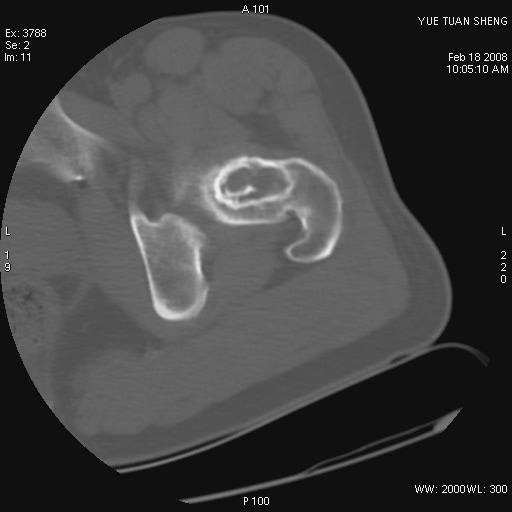

患者,男,56岁,左髋部疼痛1个月,x线:左股骨头高密度影,性质待定,右侧正常。左髋ct如图

左股骨颈区椭圆形磨玻璃样影,边缘明显硬化环环绕,其内见斑点状类钙化高密度影考虑 良性骨病-----骨纤,骨化性纤维瘤,内生软骨瘤。